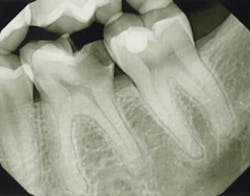

Exam/diagnosis: Tooth No. 19 was hyper-responsive to cold with no linger. The tooth presented with extensive decay into the pulp space, but was asymptomatic to both percussion and palpation. Radiographically, the periodontal ligament space and trabecular pattern were within normal limits.

PREOPTreatment options: Root canal treatment, no treatment or extraction.

Treatment: Following an inferior alveolar block and intraosseous anesthesia, access was made and caries were removed. After access, the main canals were irrigated with sodium hypochlorite and a glide path was established with hand files to working length. The dentin triangle was removed with Protaper S1 and the final instrumentation was completed using WaveOne. The two canals in the distal root joined to form a broad canal in the facial-lingual dimension and exit a common foramen. After shaping was completed in the mesial root, an isthmus of pulp tissue was identified under the microscope and a mid-mesial canal was identified following exploration of this area. However, the initial orifice was small and the canal path irregular, thereby preventing the establishment of a glide path to the apex. To open the orifice, a series of hand files was used just below the pulpal floor. It was then possible to pass a 10 file to the mid-root and the orifice opening was completed with a Vortex orifice opener size 20/08. The natural glide path was then instrumented to the apex with a 10 file and a Vortex Blue 15/04 was utilized to enhance the shape. A series of Vortex Blue instruments was used to create the final shape of 30/04. In this clinical scenario, Vortex Blue is the ideal rotary instrument system because of the cutting efficiency and combination of cyclic fatigue resistance and flexibility.